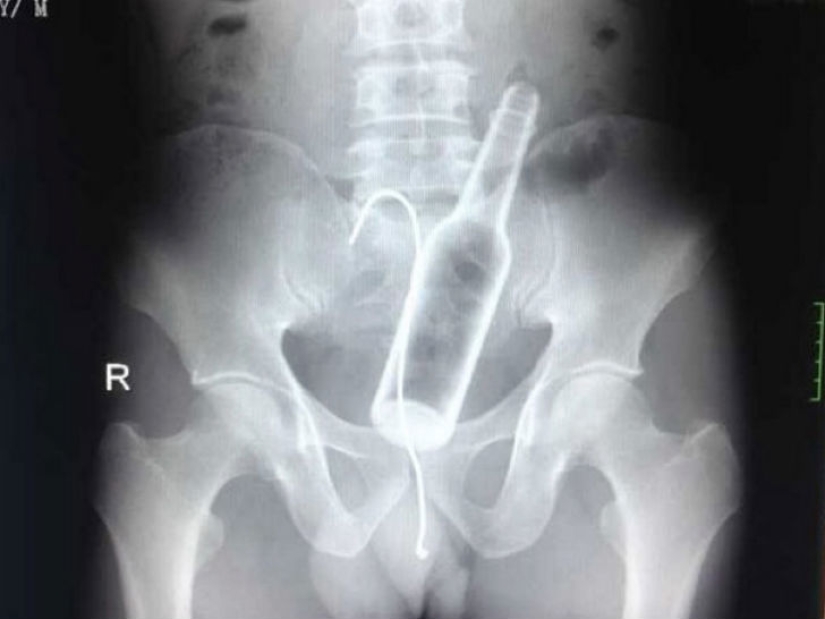

A man came to one of the Chinese hospitals with complaints of abdominal pain. Doctors took an X-ray and found a glass bottle in the stomach.